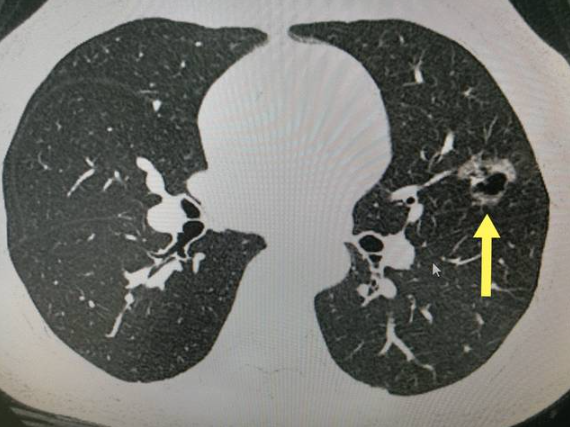

肺结节是呼吸医学中的一种内科疾病。本病的发生与感染阴感染、细胞免疫功能紊乱和液体免疫功能紊乱有关。面对这种疾病,人们应该采取充分的治疗措施,更多地了解这种疾病的病因,增强身体的免疫抵抗力,对此病是有着很重要的预防效果。肺结节是有一定大小程度越大,它带来的影响性会越强。那么,6毫米的肺部结节需要手术吗?

肺结节的严重程度与其大小有关。一旦人们的结节超过一定程度,就需要及时治疗。一般来说,5到10毫米的肺结节是小结节。6毫米肺结节不需要手术,根据一定的药物治疗可以治愈。肺结节的严重程度不仅与结节的大小有关,还与结节的良恶性有关。如果人们患有恶性肺结节,他们有一定的风险,就需要及时的手术治疗。由于这种情况是因人而异的,一般来说,6毫米的肺部结节不需要手术。面对肺结节,人们必须特别控制自己的饮食习惯和生活习惯,减少吸烟因素,否则很容易产生恶性结节。面对肺结节,人们应该采取适当的措施。一旦病情超过6毫米,要打起12分精神,观察病情是否越来越严重。